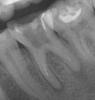

omeza Опубликовано 17 июня, 2010 Поделиться Опубликовано 17 июня, 2010 Добрый вечер! На 6 зубе гранулемы(снимок прелагаю), хирург говорит что надо удалять, ортопед лечила метапексом, но зуб от него стал ужасно болеть...Подскажите, есть ли другие пути решения или только на удаление? Ссылка на комментарий